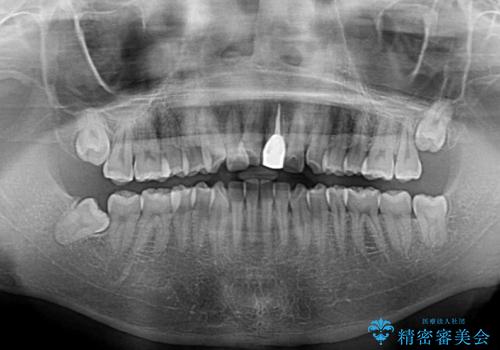

- 前歯の歯並びと不自然な色をした前歯のクラウンを気にして来院された患者様です。

上下前歯の歯列不正はインビザラインにより歯列を整え、その後に、前歯をオーダーメイドタイプのオールセラミッククラウンにて補綴治療することとしました。

初診時には、歯並びを整えることのみを検討されていましたが、歯列が整うにつれて不自然な色合いが気になるようになり、矯正治療を行ってから補綴治療をする計画を受け入れてくださいました。